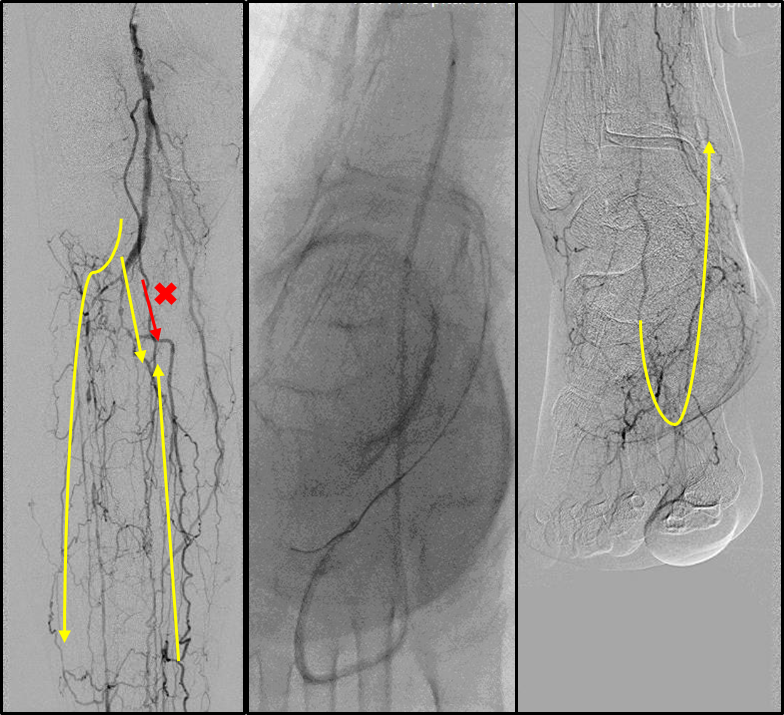

各分支 CTO 解剖特点

三大主要分支的CTO近端与远端常见位置:

总体特点:

膝下通常有单个或数个可见的流入道;

病变常为单个或多个CTO组合,总长度可达20cm;

部分患者存在踝上交通动脉或完整的踝下足底弓,为逆向开通提供可能。

逆行技术

Through pedal arch or ACA/PCA

To distal cap of CTO in target artery